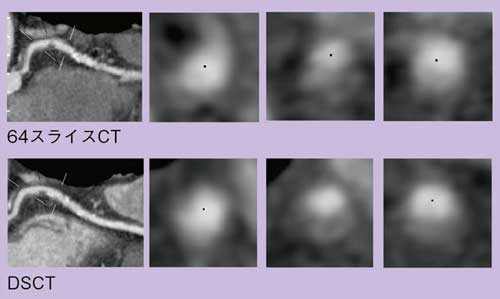

また,冠動脈プラークの検出と輝度の評価は非常に重要である。図3は同一症例における64スライスCTと,1年後のDSCTの画像であるが,時間分解能に優れるDSCT画像の方が,よりクリアにプラークを描出できていることがわかる。

図3 同一症例における64スライスCTとDSCTの冠動脈プラーク検出能の比較